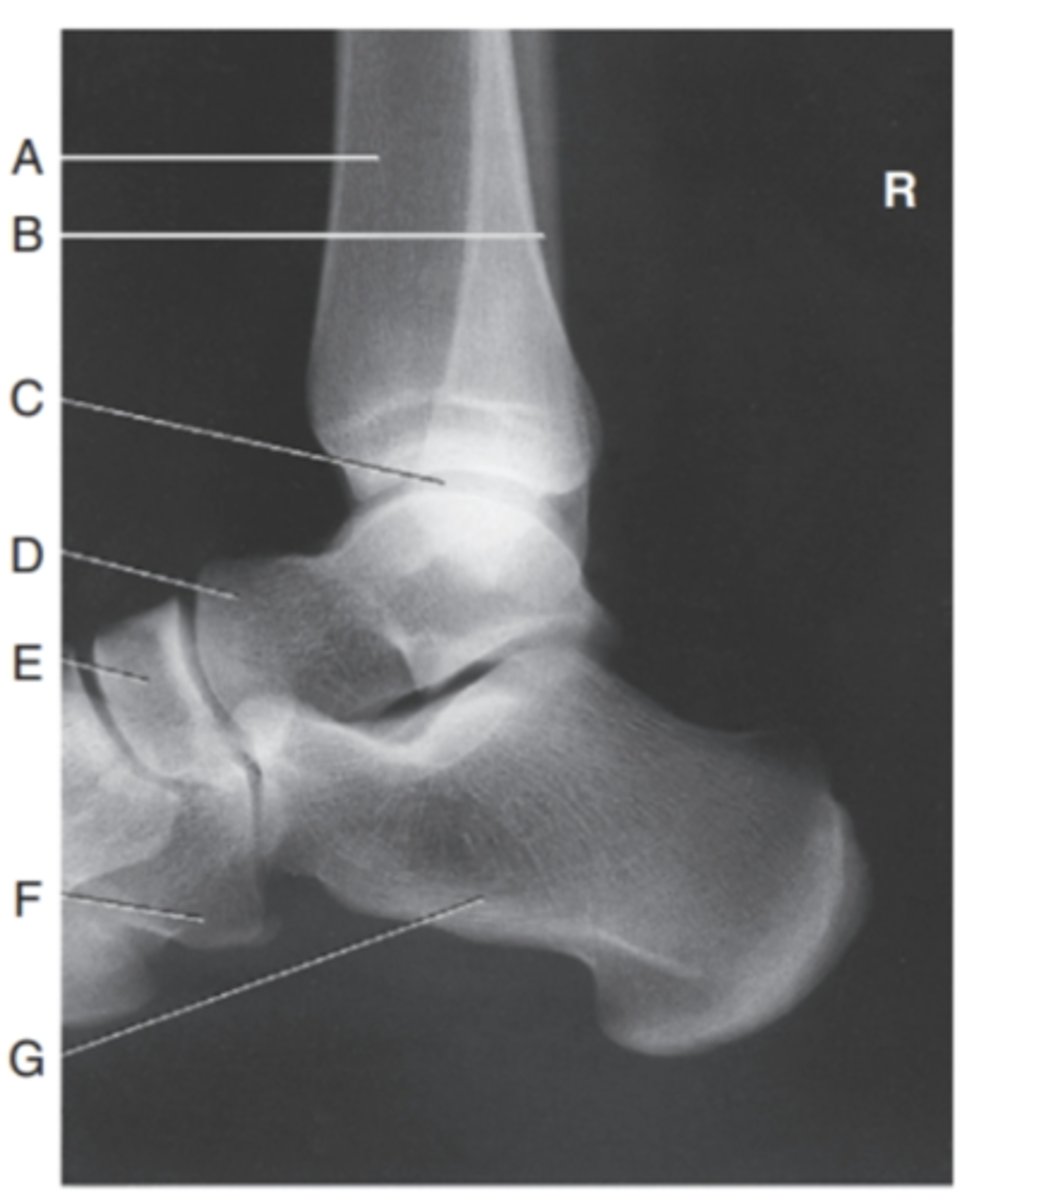

(LATERAL ANKLE) what is A?

tibia

what is B?

fibula

what is C?

tibiotalar joint

what is D?

talus

what is E?

navicular

what is F?

cuboid

what is G?

calcaneous